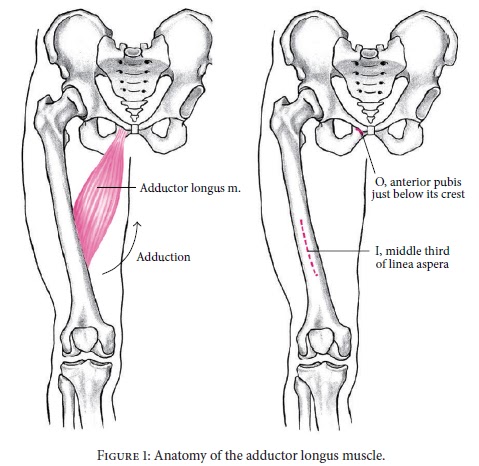

O adutor longo é um músculo longo e relativamente estreito,

de forma triangular. O músculo tem origem no ramo superior do osso púbico e insere-se

na parte média da linha áspera do fémur. As fibras musculares são estreitas na

origem e espalham-se mais para a inserção.

O ramo anterior do nervo obturador inerva este músculo. E a

sua função é a adução, rotação externa e anteversão da articulação da anca.